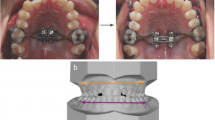

The simulation results were then used to create an individual surgical guide (ANSYS SpaceClaim software ANSYS Inc., Canonsburg, USA) for the left and right sides via CAD/CAM technique and subsequently milled (Hermle C30U, Maschinenfabrik Berthold Hermle AG, Gosheim, Germany) from PEEK (polyetheretherketone) [28, 29] (Fig. 4).

The osteotomy was performed piezosurgically at the Le Fort I level. Based on Line’s technique of osteotomy from 1975, this modified procedure leaves iatrogenic bone bridges in the area of the canines due to their pronounced root length [30]. After anesthesia, the incision of the mucosa was made paramarginally, vestibular from region 13 to 16 and region 23 to 26, with tunnelation anteriorly and posteriorly. The submucosal and subperiosteal preparation in tunnel technique extends into the infraorbital region as well as via the zygomaticoalveolar crest to the retrotubar maxillary region and into the pterygopalatine fossa. The surgical guide for one side was then inserted (Fig. 5). Subesquent osteotomy of the vestibular wall of the maxillary sinus in accordance with the recesses of the respective surgical guide (right vs. left) was performed. The bone incisions through the maxillary bone were started laterally following the guide with a piezosurgery approach at the zygomatic insertion, and after opening the maxillary sinus, they were moved medially through the facial maxillary sinus wall and the nasal aperture. The pterygomaxillary separation was performed with a special extremely curved Kawamoto chisel from the dorsal tunnel edge, followed by vertical incision of the upper lip frenulum and opening of the midpalatal suture piezosurgically and with the chisel. The distractor was inserted at the pre-planned position via a guide in the palate with a horizontal incision and anchored with a fixation screw on each side. Wound closure was undertaken with suturing. The medial and dorsal walls of the maxillary sinus remain intact during the osteotomy. The TPD was checked for proper function by opening the device to 3mm. Then, the TPD was turned back to 1mm of opening. After a short healing time, the appliance was activated daily by the patient by 0.5–1mm until desired expansion was achieved.